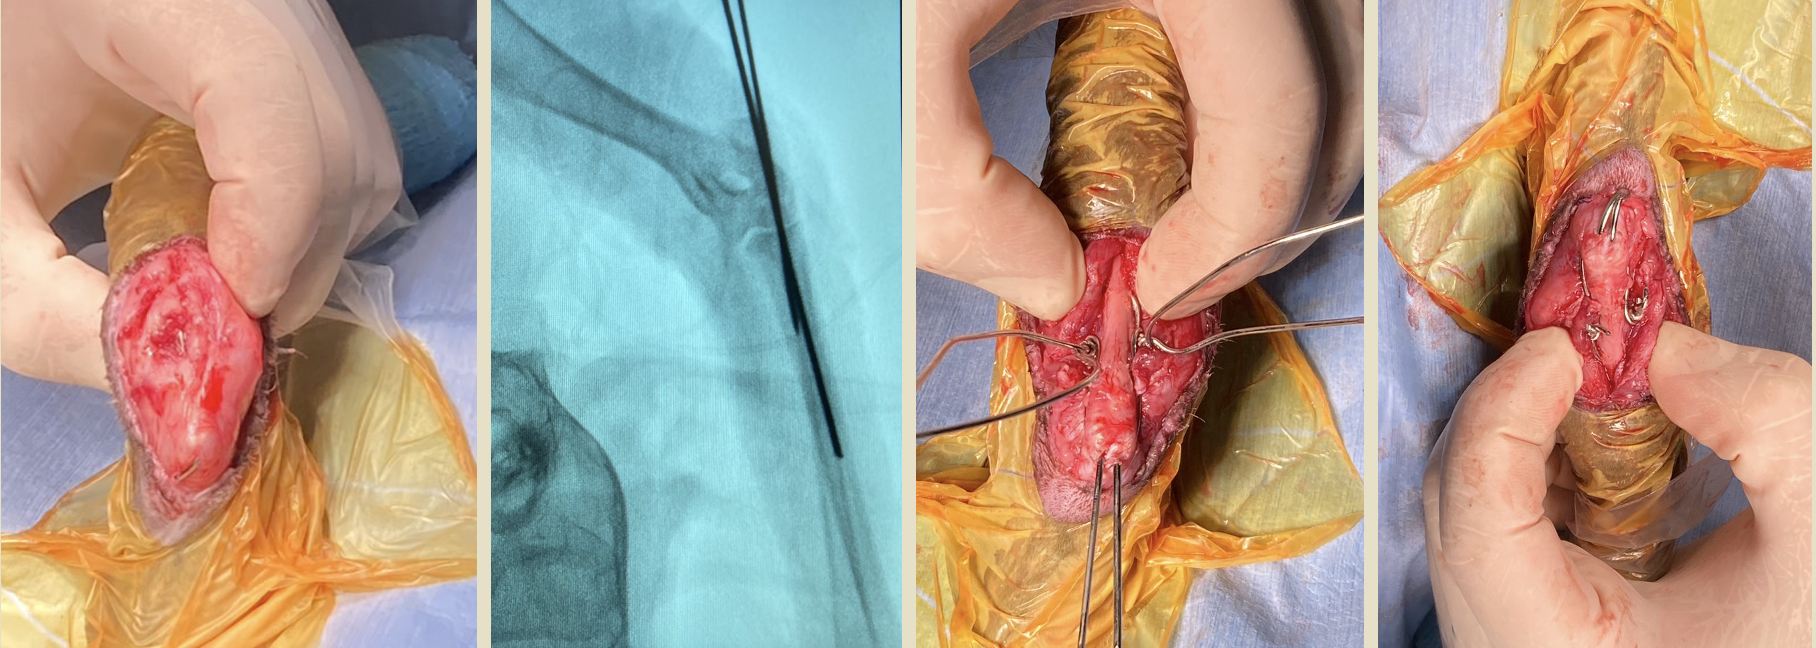

左肘頭骨折と診断し、髄内ピンとサークラージワイヤーによるテンションバンドにより固定した

after